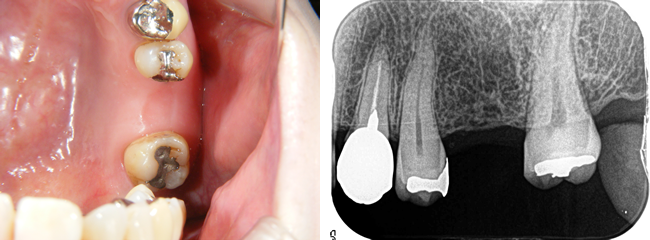

口腔内診査、レントゲン、CTなどから、骨量は十分と判断し歯肉を開かずに埋め込みすることになりました。

歯肉を開いていないので、出血もなく縫っていません。

1本の埋め込みなら、15分程度で終了します。この状態で3~4ヶ月待ちます。

インプラントと骨が結合したら、歯型を採って、歯冠になる部分を作ります。